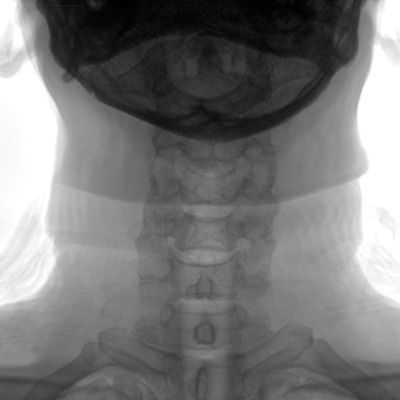

臨床適用科室:骨科、普通外科、矯形外科、創(chuàng)傷外科、泌尿外科、脊柱外科、疼痛外科、消化科、婦科等科室。

大尺寸動態(tài)平板探測器,高DQE、低噪聲、圖像清晰。采用多分辨率圖像增強(qiáng)處理技術(shù),不同部位不同圖像處理算法,滿足客戶多樣化的需求。

多角度自由旋轉(zhuǎn),滿足患者復(fù)雜擺位需求。